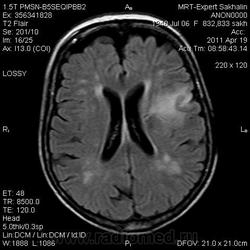

склоняюсь к кровизлиянию в левой теменной долей, начало перехода острой стадии в раннюю подострую( по периферии определяется повышение МРС по Т1 ВИ -метгемоглобин). Справа -старые кортикальные постишемческие глиозно-атрофические изменения. Контрастируется , вероятно за счет формирования участков ангионеогенза.

Это демиелинизирующий процесс, острая стадия, причем с геморрагическим пропитыванием в центре пораженных участков. В принципе, соответствует тяжелому рассеяному склерозу, хотя может быть и геморрагическая форма ОДЭМ. Также могут быть мозговые проявления системного васкулита: надо знать анамнез.

На фоне ДЭП изменений МР-картина ОНМК по ишемическому типу в бассейне ЛСМА с участками геморрагического пропитывания. Аналогичный участок но в более поздней фазе в задних конвнкситальных отделах правой теменной доли.

О.С., я согласен, что контрастирование нехарактерно для ОНМК, ведь в подострую стадию инфаркта наблюдается, как правило, гиральный тип усиления. Плюс, на ОНМК непохоже то, что поражено почти только белое вещество, а кора интактна. И потом, при такой локализации инфаркта обязательно должна быть яркая клиника, и уж никак не только "головная боль".

Что касается снимочков мне кажется что зона патологического сигнала в левой гемисфере можно расценить как подострую стадию ОНМК с геморрагическим пропитыванием, справа как последствия ОНМК. При чем множественные очаги скорей всего как проявление ХМНК. И обязательно рекомендовать контрольное МРТ в динамике . Если это действительно ОНМК на фоне лечения отек уйдет и будет формированиться зона кистозно-глиозных изменений, а если отек будет нарастать значит надо думать о объемном процессе.

ОНМК по геморрагическому типу, почти классика.